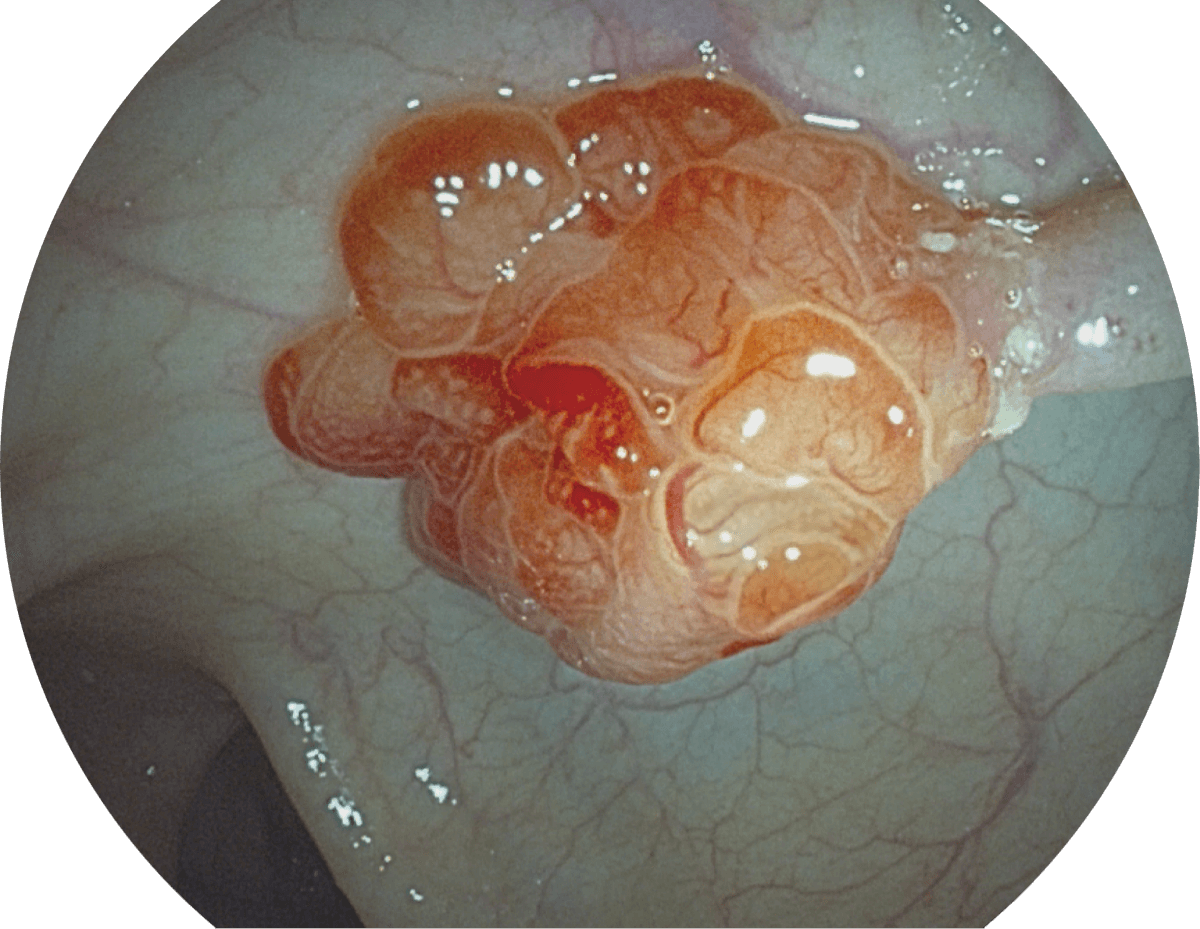

• WL

• SFI

• VIST

图像具有高亮度、高黏膜血管颜色对比度的特点,且不改变粘液、食物残渣、粪便的基本颜色,可在中远景下进行观察,助力消化道早期疾病的诊断。

强调浅层黏膜结构的同时,保证照明亮度和提升浅层微血管与中层血管颜色对比度,病变边界更清晰。